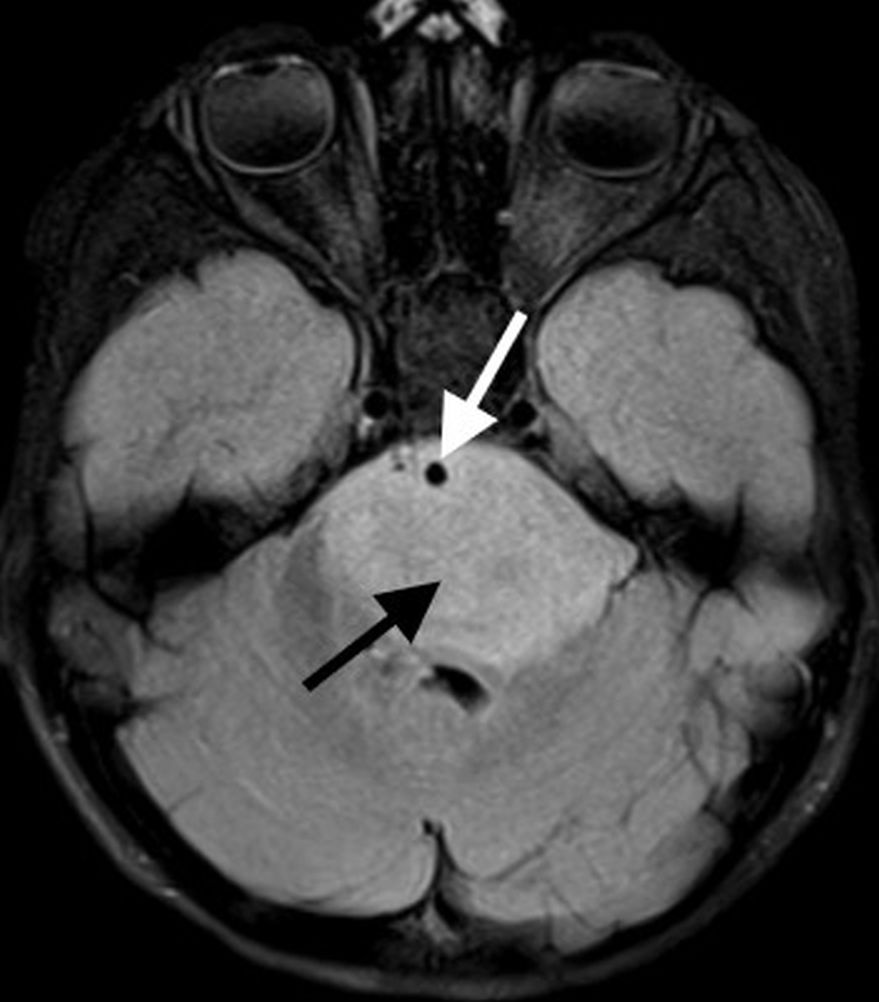

On MR imaging, DMGs present as a diffuse, ill-defined, T2 hyperintense, expansile masses centered within the pons. The degree of enhancement is variable, often absent at initial presentation and typically patchy when present (Fig. 3).

Peripheral enhancement commonly occurs along margins of central necrosis, which occurs more frequently after radiation therapy [25]. Intralesional hemorrhage is uncommon, but areas of hemosiderin deposition may be seen on susceptibility-weighted sequences. Focal areas of restricted diffusion develop in the majority of cases. The presence of central necrosis, diffusion restriction, or enhancement at the time of initial diagnosis has been shown to portend a worse prognosis [24].

Extrapontine spread is common throughout the brainstem, into the thalami and adjacent structures, through the cerebellar peduncles, and into the cerebellar hemispheres. Exophytic components engulf the basilar artery anteriorly and efface the fourth ventricle posteriorly. Disseminated metastatic disease is uncommon, though may be seen occasionally.